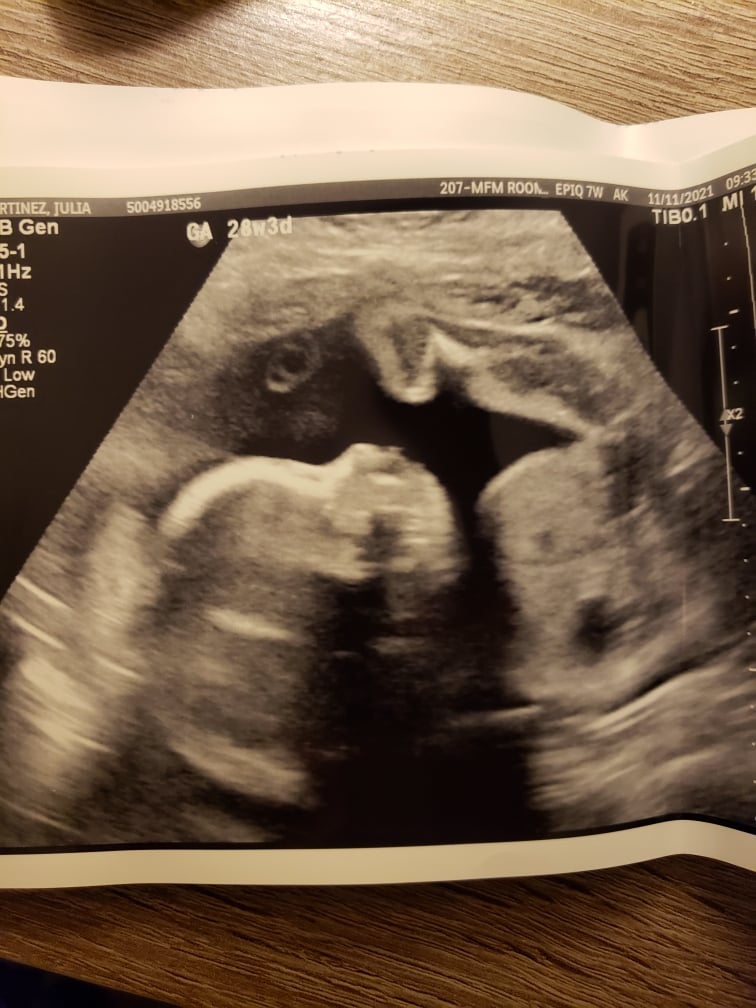

Aside from that, baby is looking good.